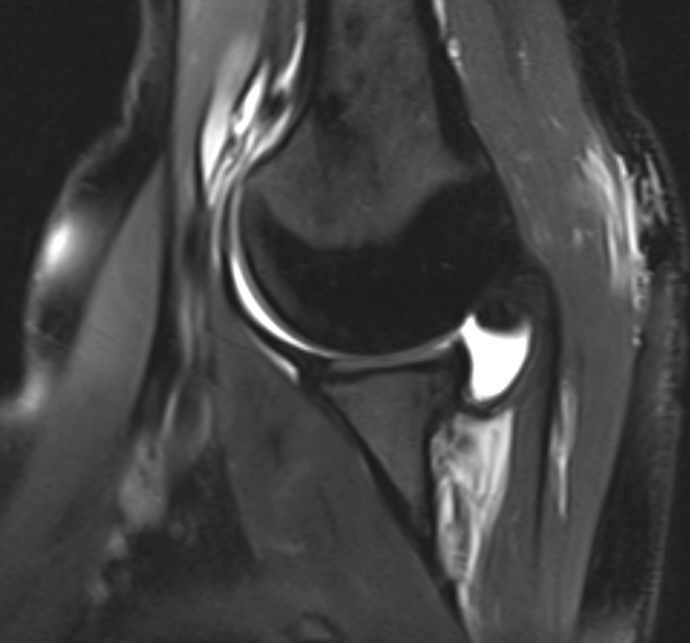

3. Normal ABER view shoulder arthrogram